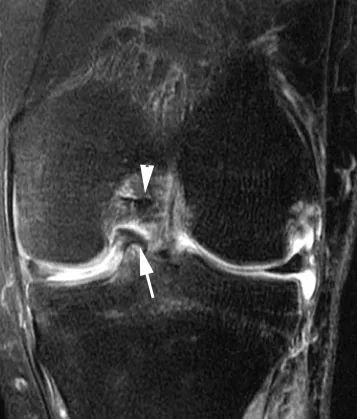

Perpendiculaire au plan tibial et le long de la circonférence du ménisque.Ceux-ci affectent plus fréquemment le ménisque médial.Une blessure complète est considérée comme instable et divise le ménisque en segments médial et latéral.Le niveau de numérisation comprend également le corps du ménisque latéral et la corne postérieure du ménisque, ce qui est facile à mal diagnostiquer comme une déchirure de la poignée du barillet, ce qui est plus susceptible de se produire lorsque l'articulation du genou est tournée vers l'extérieur.Combiné avec des images sagittales, une déchirure en anse de tonneau peut être exclue (Figure 3).

A. IRM coronale, la flèche pointe vers la corne postérieure du ménisque latéral, qui peut facilement être confondue avec une fissure en anse de barillet ;B. Lors de l'exécution d'un balayage IRM selon la position indiquée par la ligne pointillée sur la figure, une pseudo déchirure de la poignée du barillet apparaîtra.

D'autres signes IRM ont été validés, tels que l'absence de nœud papillon, le signe du ménisque inversé ou des fragments méniscals déplacés directement dans la région intercondylienne sur les images frontales millimétriques (Fig. 9) ou axiales.

Figure 9 Anse de seau disloquée dans la fente.Vue frontale pondérée PD après suppression de la graisse.Le fragment de ménisque disloqué (flèche) est en contact avec le LCA (flèche).